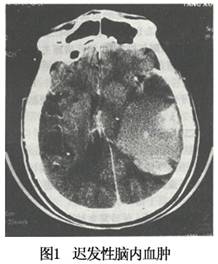

迟发性外伤性脑内血肿在文献中虽早有报道,但自CT扫描应用以后,才较多地被发现,并引起人们重视。自从CT问世之后,对迟发性外伤性脑内血肿的概念已较明确,即头部外伤后,首次CT检查未发现脑内血肿,经过一段时间后再次检查始出现脑内血肿者;或于清除颅内血肿一段时间后又在脑内不同部位发现血肿者。本病的临床特点可以概括为中、老年病人,减速性暴力所致中至重型颅脑损伤,伤后3~6天内症状和体征渐次加重,或有局限性癫痫,意识进行性恶化,特别是曾有低血压、脑脊液外引流、过度换气或强力脱水的病例,应及时复查CT。

大部分迟发性外伤性脑内血肿患者的原发伤不重,病人在经过一阶段好转或稳定期,数天或数周后又逐渐或突然出现意识障碍,出现局灶性神经体征或原有症状体征加重,部分患者的原发伤可以很重,伤后意识障碍亦可一直无改善或加重。复查CT才证实为迟发性脑内血肿。